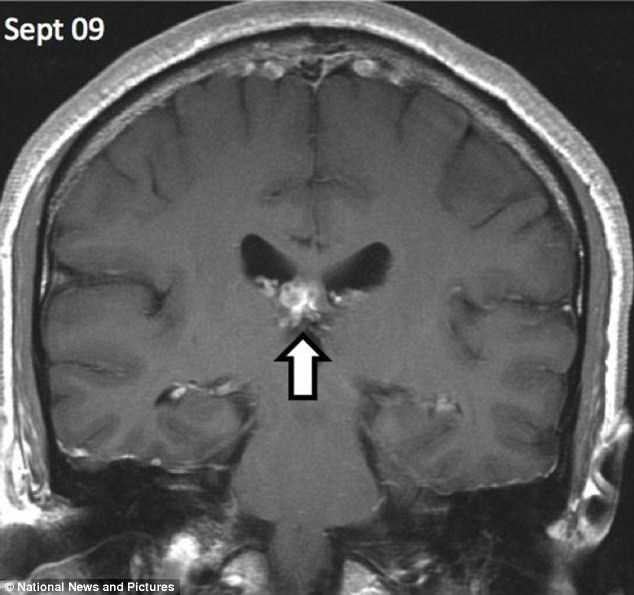

| Con sán dài 1cm đã đào sâu tới 5cm vào não bệnh nhân. (Nguồn: DM) |